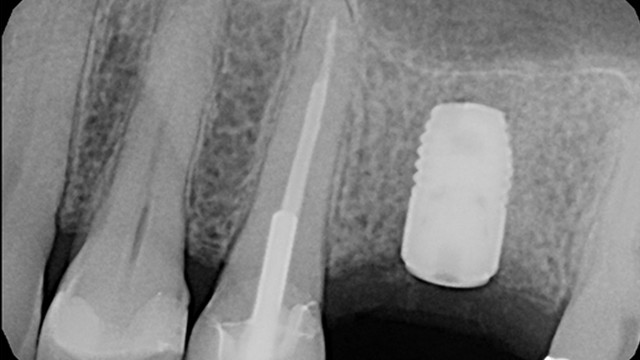

The surgical guide is now used to place the implant in the exact location that was planned digitally.